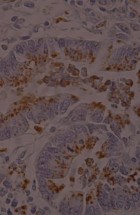

The Department’s main activities encompass research and specialized tasks. It focuses on clinical, pathoanatomical, pathohistological, immunohistochemical, and molecular diagnostics of diseases in both domestic and wild animals, including reproductive pathology. Operations within the department are structured around fieldwork and laboratory analyses.

- Performing pathohistological, cytological, immunohistochemical, and molecular diagnostics.